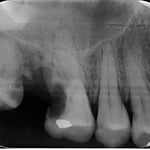

一番左の写真で、どこに虫歯があるかわかるでしょうか?虫歯の進展度を知るためにはレントゲンは欠かせませんが、レントゲンを撮影しなくても、自然光に近い明るい視野の下で、拡大してじっくり観察すれば、早期発見、早期治療に最も役立つのが顕微鏡です。これも当院のベテラン衛生士が最初に気付いた虫歯です。自覚症状がでてからでは、歯髄を保存できる可能性が低くなってしまいます。この症例も、歯髄を除去ぜす(根管治療をしないで)保存できました。

自然光に近い明るい光の下で、拡大して、じっくり観察しなければ、早期に発見出来ない虫歯が多いのです。